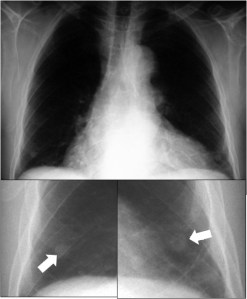

SIGNO DEL TUMOR FANTASMA O TUMOR EVANESCENTE

Signo que describe al derrame pleural atrapado en la cisura menor, especialmente en pacientes con insuficiencia cardiaca. El derrame loculado en la proyección posteroanterior se ve como una lesión nodular o masa que simula un tumor sólido (imagen superior). Sin embargo, la evolución rápida hacia la desaparición de esta lesión sugiere que se trata de derrame.

Vemos en las imágenes un tumor fantasma que desaparece en el control realizado cinco días más tarde.

En la primera imagen, la presencia de derrame pleural asociado y el engrosamiento del resto de la cisura menor, visible como una línea superpuesta al tumor fantasma, sugieren el diagnóstico.